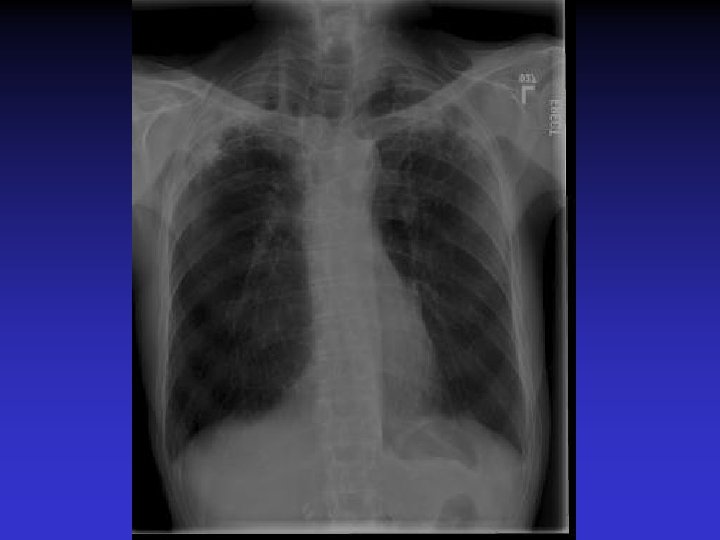

NTM lung disease n n MAC, M. kansasii, M. abscessus >50 years, ? M vs. F Symptoms n variable, nonspecific n chronic or reoccurring cough n sputum production, fatigue, malaise, dyspnea, fever, hemoptysis, chest pain, wt loss n more constitutional symptoms with advancing disease n evaluation complicated by sx of coexisting lung disease CXR n Fibrocavitary – often like MTB, but may be dense airspace dz or solitary cavity w/o cavitation n Nodular/bronchietatic – typical MAC, usu. mid-lower lung fields, +/- cavitation

M. simiae n n M. simiae may be confused with MTB as it is the only niacin-positive NTM Maoz et al. compared pts in Israel with M. simiae vs MTB. Pts with M. simiae: n More females, older age n Higher rates of smoking, COPD, other dz (DM, CAD, cancer), immunosuppressive drugs n Less HIV n Blunted symptoms n More noncavitary infiltrates in middle/lower lobes Most M. simiae isolates were contaminants Treatment with clarithromycin, ethambutol, rifabutin, and streptomycin (with modification for sensitivities)